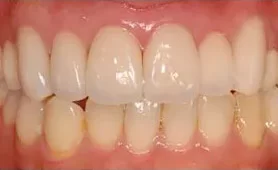

• 治療前

• 治療後